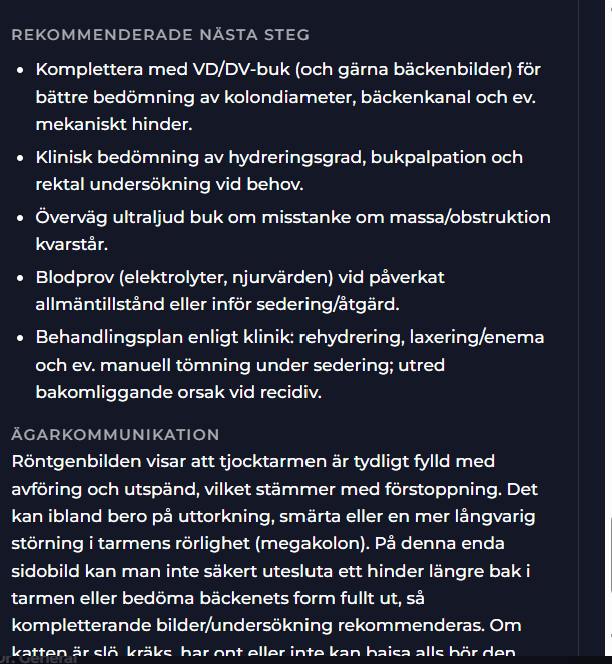

I Stetoskåpet med Visuella Fynd (Röntgen) finner du ett strukturerat remiss-svar och rekommendationer. Din AI-doktor hanterar dessa resultat och återupptar chatten med dig. Du kan när som helst klicka på olika submenyer i Steoskåpet för hela statusen i ärendet.

I Visuella fynd (Stetoskåpet) finner du det kompletta remisssvaret. I remisssvaret kan du du titta på den strukturerade labrapporten samt läsa Labora´s svar på frågeställningen. Labora kommer svara både övergripande och i detalj för de enskilda biomarkörerna smat ge en rekommendation till din chatt AI doktor.

I din huvudchatt så fortsätter ärendet kontinurligt och AI doktorn kan ställa nya frågor beroende på statusen i ditt ärende som t.ex resultatet från inkommande remissvar från Radiologica

I detta simulerade fall finns förslag på remiss, diagnos, rekomendation, akutläge etc i stetoskåpet.